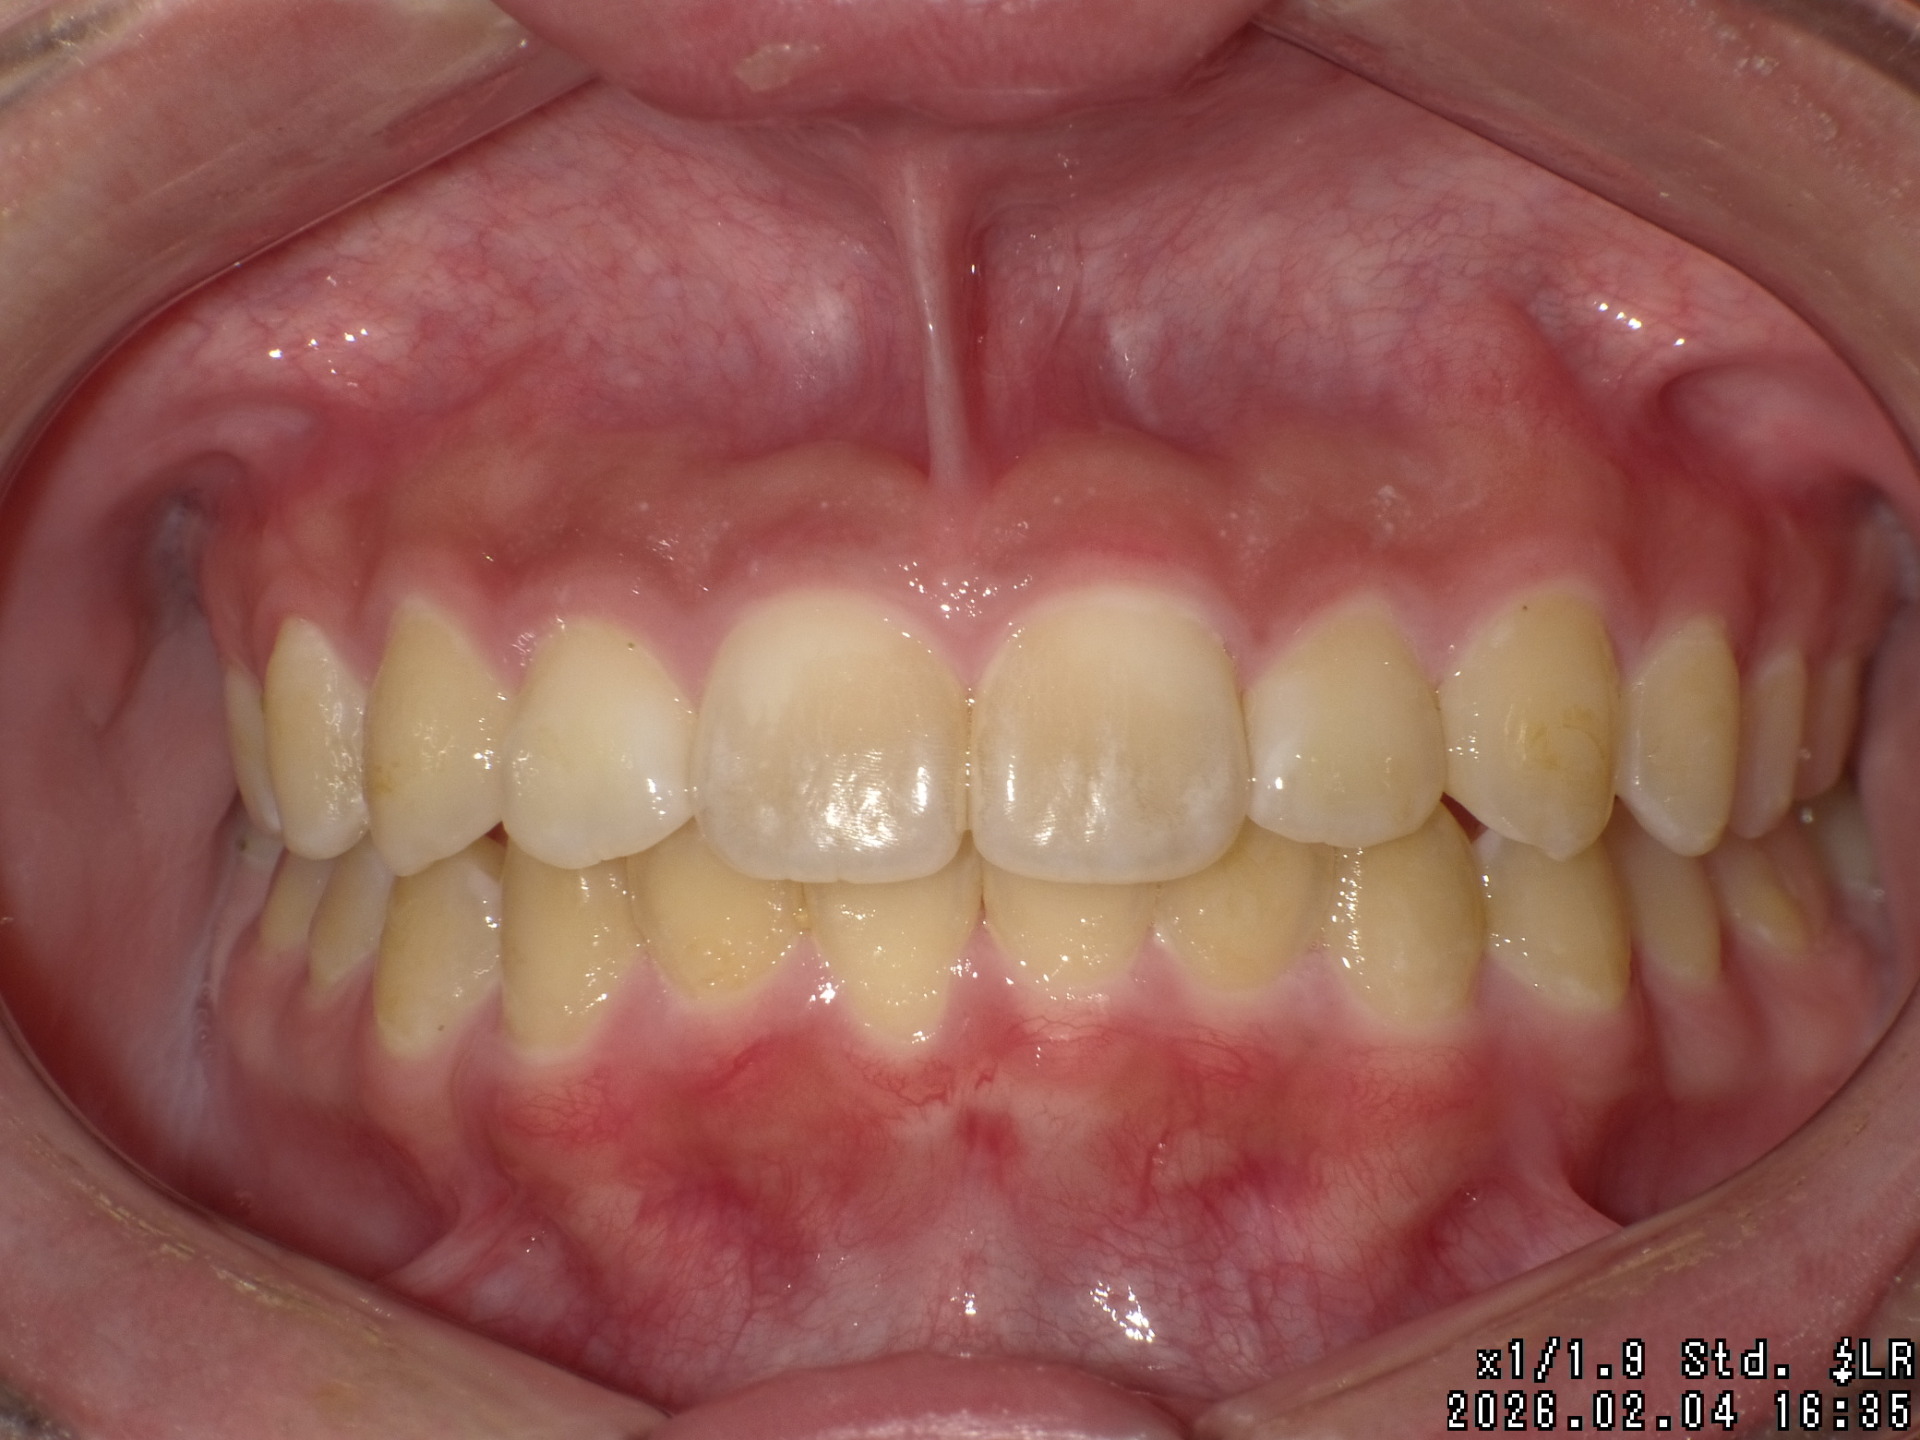

矯正前

| 症状 | 上顎前突 過蓋咬合 |

|---|---|